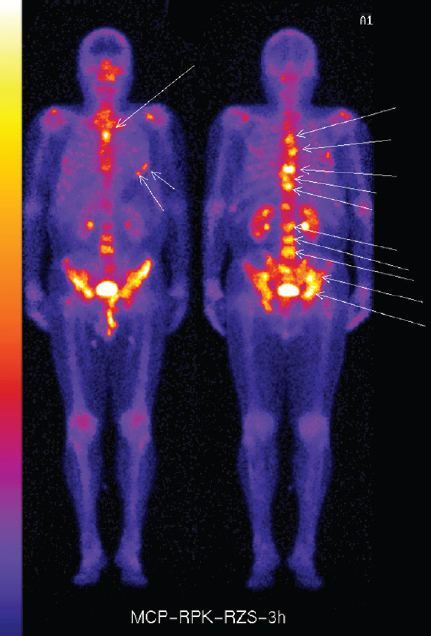

Преимущество такого подхода отчётливо проявилось в области разработки, проведения КИ, регистрации и внедрения в широкий оборот РФЛП для первичной диагностики, планирования и контроля лечения костных метастазов у больных с различными онкологическими заболеваниями. Данные РФЛП в РФ и в мире зарегистрированы и выпускаются в виде лиофилизированных наборов, содержащих в качестве таргетного лиганда бисфосфонат, а активный изотоп для мечения 99mTc зарегистрирован в качестве субстанции и получается в виде элюата из генератора 99mMo/99mTc. В настоящее время за рубежом для остеосцинтиграфии методом ОФЭКТ/КТ широко используется РФЛП 99mTc-MDP, в РФ зарегистрированы и используется в рутинной онкологической практике аналог РФЛП «Технефор, 99mTc» (ООО «Диамед») и инновационный отечественный РФЛП «Резоскан, 99mTc» (АО «Фарм-Синтез»), в котором в качестве таргетного лиганда используется золедроновая кислота, обладающая наибольшей аффинностью к костным метастазам, как остеобластического, так и остеолитического типа [27]. На рис. 9 представлены остеосцинтиграммы больного с метастатическим РПЖ, выполненные РФЛП Резоскан, 99mTc в процессе КИ 3 фазы. Данные остеосцинтиграфии показали высокую селективность и специфичность РФЛП, составляющие более 90%. Обращает внимание способность РФЛП выявить не только метастазы осевой части скелета, но и лицевой кости [27].

Рис. 9. Визуализация диссеминированного метастатического поражения осевого скелета и лицевой костей при проведении остеосцинтиграфии РФЛП Резоскан, 99mTc / Fig. 9. Visualization of disseminated metastatic lesions of the axial skeleton and facial bones during osteoscintigraphy RFLP Rezoscan, 99mTc

РФЛП «Резоскан, 99mTc» был зарегистрирован в виде лиофилизата для приготовления раствора для внутривенного введения. В связи с тем, что содержащаяся в РФЛП Резоскан, 99mTc однократная доза золедроновой кислоты составляет 0,3 мг и на порядок ниже принятой терапевтической дозы, равной 4 мг, а доза 99mTc выбиралась в пределах установленного и принятого диапазона излучения, регистрационное КИ было проведено без 1 фазы с общим протоколом и дизайном 2–3 фазы, что обеспечило ускорение регистрации и вывод РФЛП в оборот.

В настоящее время зарегистрированные в РФ два РФЛП – Технефор, 99mTc и Резоскан, 99mTc широко используются в рутинной онкологической практике, в связи с доступностью, простотой приготовления в клинике, обеспечивая потребность онкологических центров и диспансеров без участия в обороте иностранных остеотропных РФЛП.